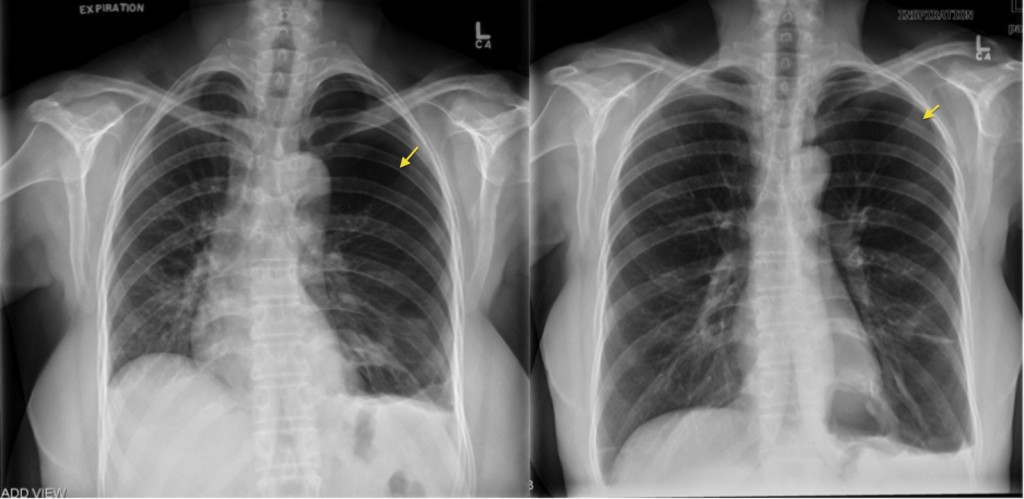

Chest expansion score which represents the circumference magnitude of the thoracic cage is used for a target when treating patients with respiratory disease It represents a scan performed with the patient on supine and images obtained at the end expiration It is a useful method for detecting small airways obstructive lung disease

This may result from a poor inspiratory effort or any other condition that prevents full inspiration This patient s chest x ray is normal in full inspiration In relative expiration the cardiac Results The breathing with mainly inspiration group BMIG showed significant differences in chest size during inspiration CSI chest expansion values CEVs forced vital capacity

Pneumothorax Expiration Radiology At St Vincent s University Hospital

Pneumothorax Expiration Radiology At St Vincent s University Hospital

Chest X Ray